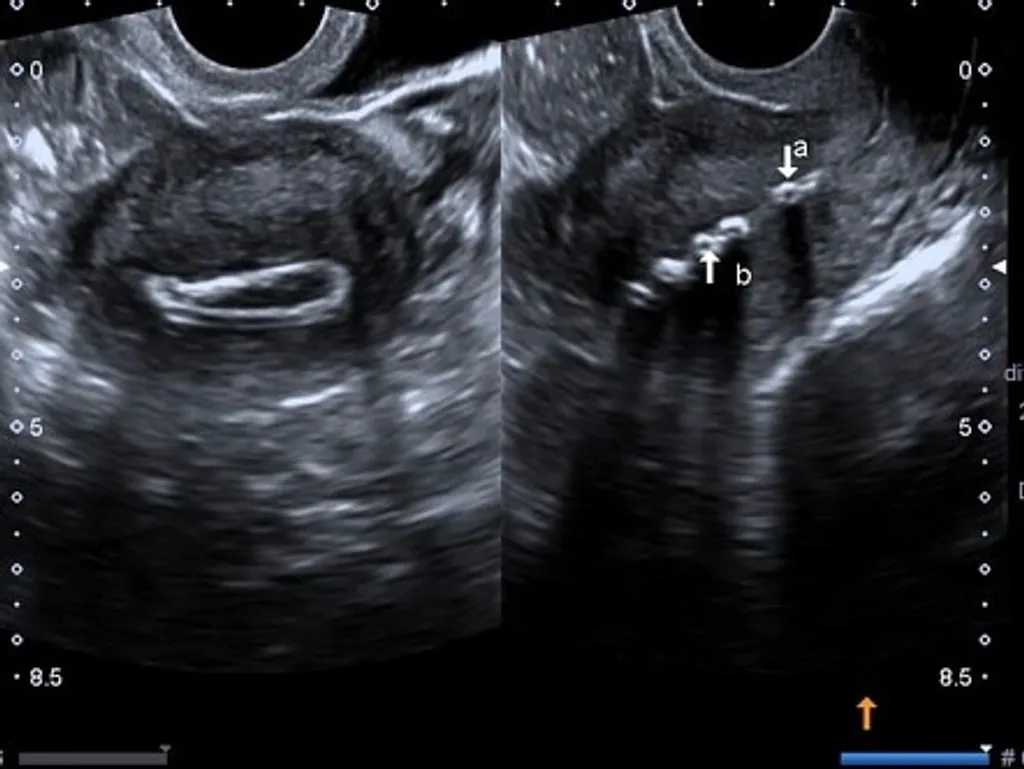

1975-ൽ ലിപ്പിസ് ലൂപ്പിന് പകരക്കാരനായയി കോപ്പർ ടി (Copper T) ഇന്ത്യയിൽ അവതരിപ്പിക്കപ്പെട്ടു. അത് സ്ത്രീകൾക്ക് വളരെ ഇഷ്ടപ്പെട്ട ഒരു താൽക്കാലിക ഗർഭനിരോധനമാർഗ്ഗമായിത്തീർന്നു. ക്രമേണ ജനനനിരക്ക് കുറയ്ക്കാനുള്ള സമ്മർദ്ദം കൂടിയതോടെ, വന്ധീകരണശസ്ത്രക്രിയ (sterilisation-tubectomy) സ്ത്രീക ളിൽ സ്ഥിരമായ ജനനനിയന്ത്രണത്തിനുള്ള പ്രധാന മാർഗമായി മാറി. ഇന്നും ഇത് ഇന്ത്യയിൽ സ്ഥിരമായ സ്ത്രീ ഗർഭനിരോധനത്തിനുള്ള ഫലപ്രദമായ മാർഗമായി തുടരുന്നു.